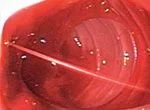

Endoscopy can provide an accurate diagnosis of conditions such as a bleeding duodenal ulcer.

In an upper endoscopy, the physician passes an endoscope through the mouth and into the esophagus, stomach and duodenum.